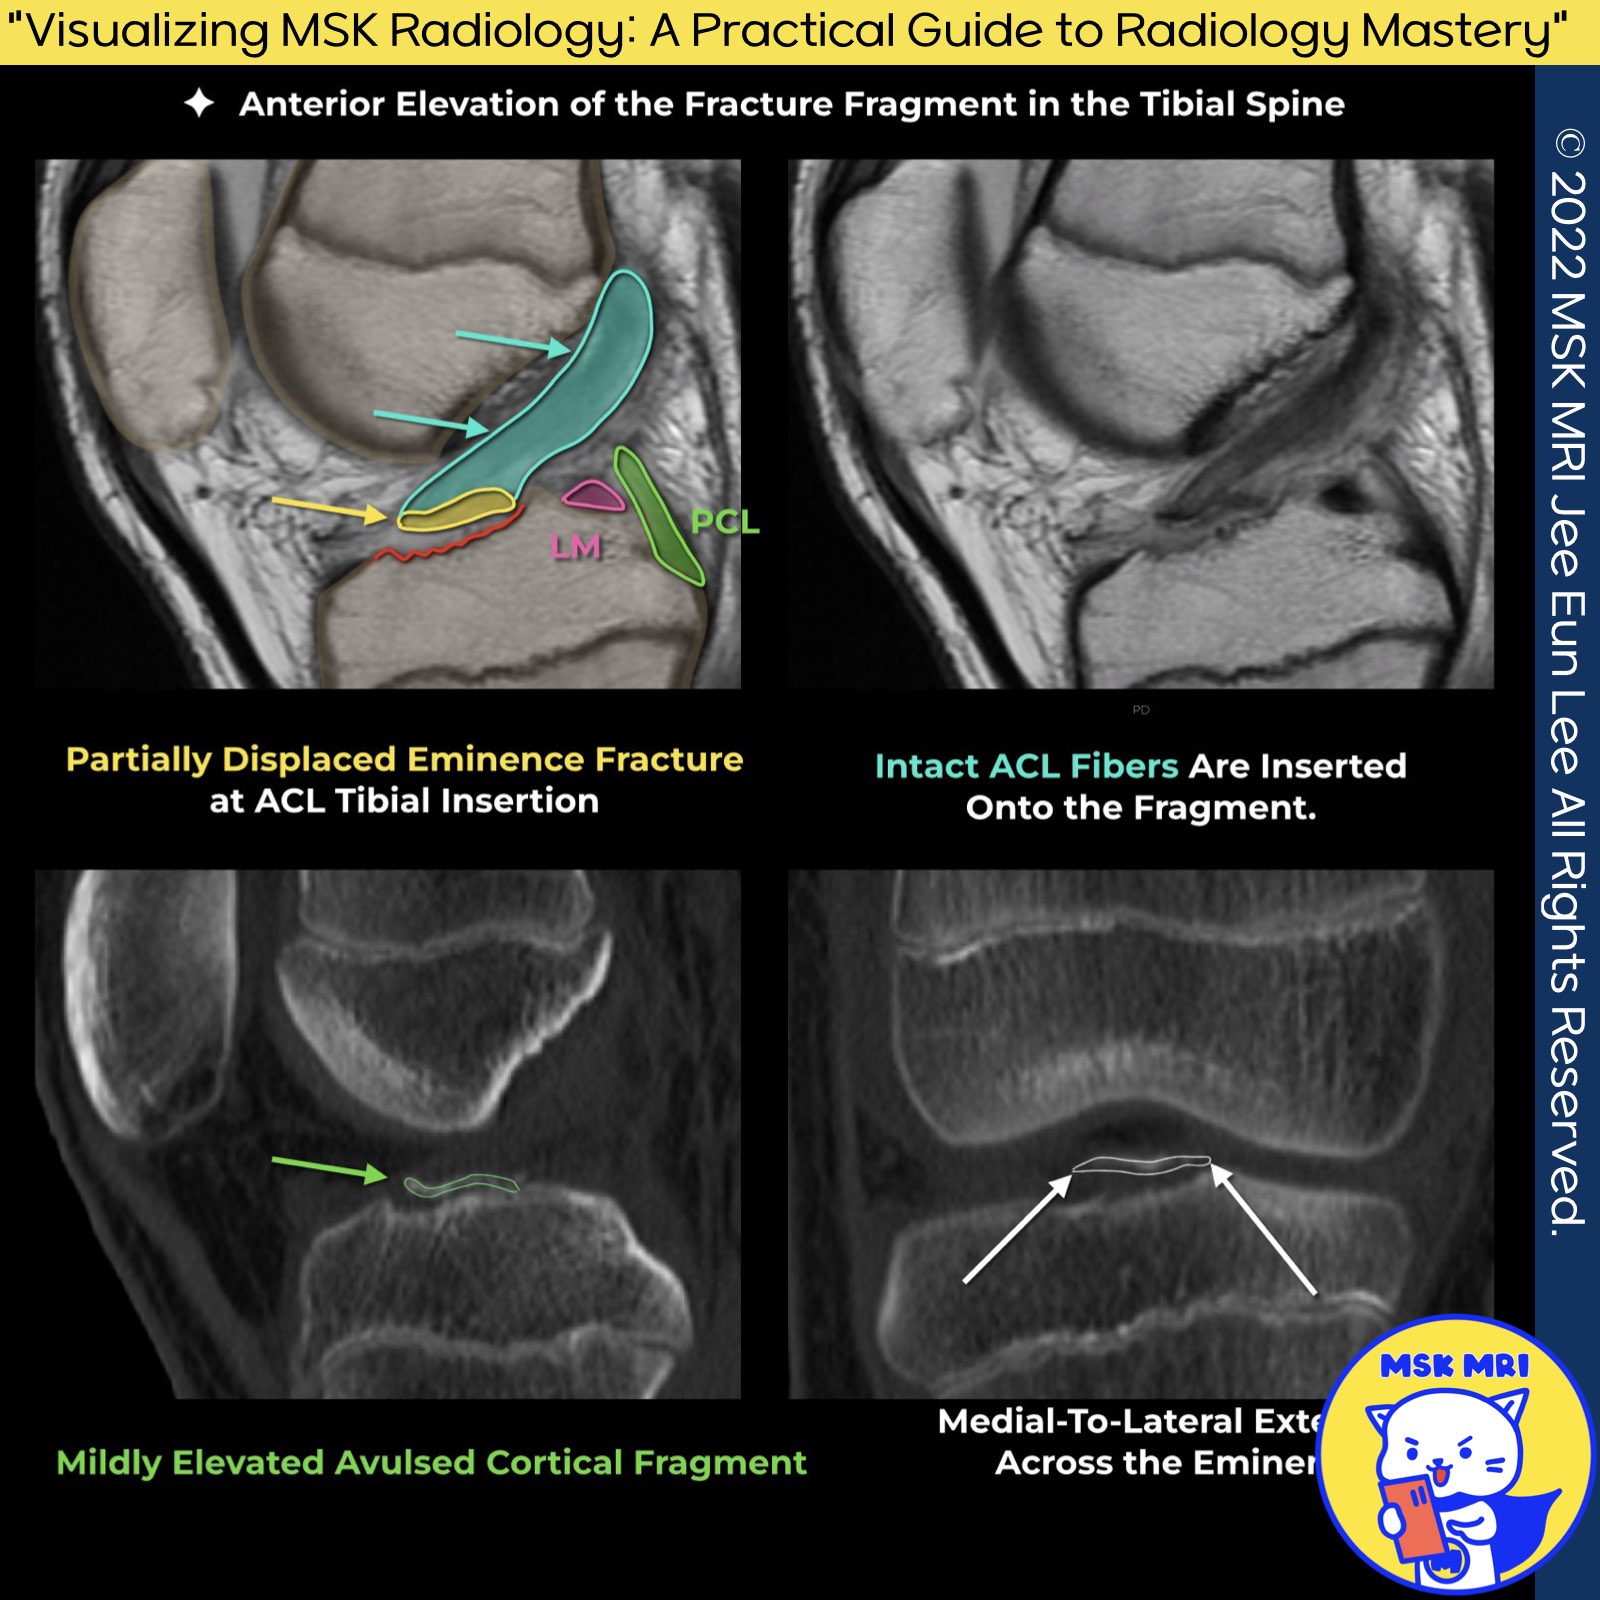

✅ Meyers and McKeever Classification System for Tibial Spine Fractures

- Type I Injury:

Characterized by a minimally displaced fragment. This type of injury typically responds well to conservative treatment methods. - Type II Injury:

This subtype features an anterior elevation of the fracture fragment, indicating a more significant displacement compared to Type I. - Type III and IV Injuries:

Both these categories signify the complete separation of the fragment from the tibia, with Type IV also incorporating either a rotational component or comminution of the fragment.

✅ Treatment Recommendations:

- Type I Injuries: Given their minimal displacement, conservative treatment is usually sufficient.

- Type II to IV Injuries: Arthroscopy is recommended and necessitates internal fixation to ensure proper healing and restoration of function.